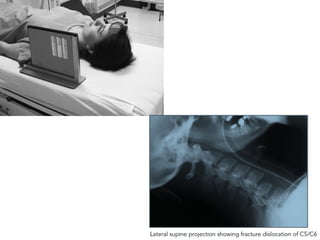

Cervical Spine-Trans-Lateral

• Make the patient to lie on the x-ray table in supine position.

• Hands are kept at side of the body.

• Ensure there is no rotation of the head & neck without much

pressure to the injury neck & foam pads are kept for immobilization.

• Radiation Production given to the patient.

Tube Centering

• Center to the horizontal beam to the cassette at level of C4.

Cassette centering

• Cassette is kept at side of the shoulder of one inch above

the pinna.